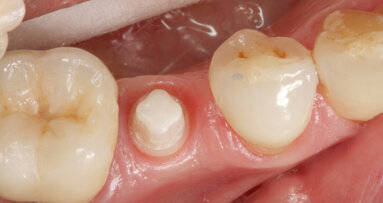

Po naskenování modelů byl návrh léčebného plánu odeslán ke zhotovení zámků a drátěných oblouků. Protože byla plánována extrakce zubů 14, 24, 34 a 44, byly na zámky 17, 27, 37 a 47 požadovány háčky k usnadnění zavádění el. řetízků používaných ve fázi uzavírání mezer.